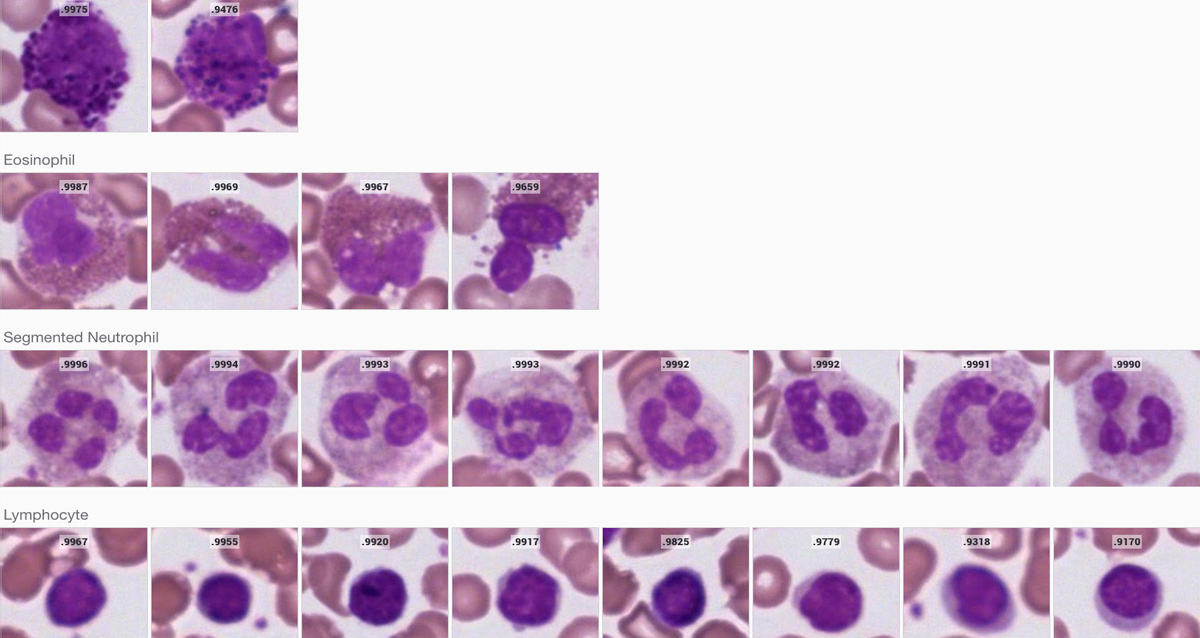

The Techcyte Blood Differential uses deep machine learning to identify in 30 seconds the mono layer, and classifies white blood cells and red blood cells into the following categories:

• Segmented neutrophils

• Eosinophils

• Lymphocytes

The Techcyte Blood Differential analyzes any good-quality 40x image. Slides must be prepared using a May Grünwald Giemsa, Wright Giemsa, or Giemsa stain.